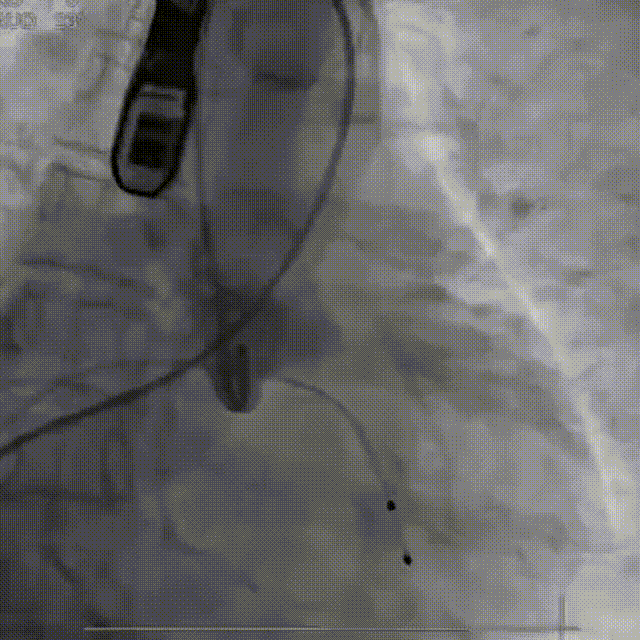

从三叶瓣重度钙化到二叶瓣畸形的根部解剖,从单纯主动脉瓣反流到入路极端迂曲挑战的案例。TaurusOne凭借其优异的柔顺性,支撑力强及内外层双侧裙边的特点,都能从容应对复杂的临床患者解剖结构。从患者的临床选择到术后的长久获益,从手术入路的种类到术中操作的注意事项,从围术期卒中的循证医学到术后的抗凝抗栓用药规范,在线专家共同交流彼此中心的围术期TAVR经验和分享现阶段经导管主动脉瓣置换的诊疗策略。针对当前TAVR领域多个热点学术问题进行了热烈的讨论,现场可谓精彩纷呈、高潮迭起。专家们纷纷借此契机相互交流探讨,分享各自的单中心经验,力求进一步提升TAVR手术的安全性和有效性,为主动脉瓣相关疾病的患者带来长远综合获益。